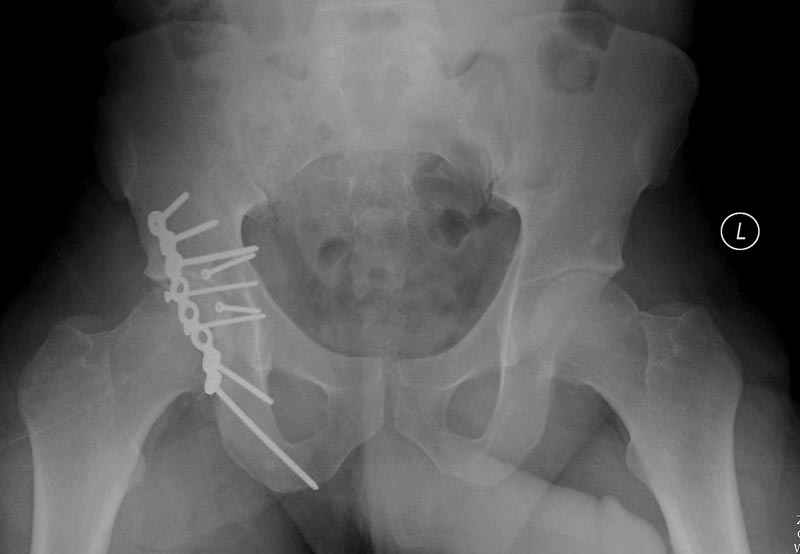

сустава, репозиция вывиха (N4), фиксация фрагмента 2.7(4) мм шурупами и допольнительно реконструктивной пластиной на 8 дырок, фиксация 3.5мм шурупами проксимально и дистально.

Интраоперционные N5 косая запирательная и N6 подвздошный снимок

11:50 больной в послеоперационной, рентгенограмма N7, компьютерная томограмма в тот же день N8-10